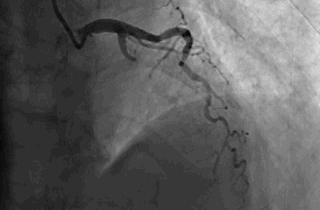

闭塞的前降支血管开通了,心肌的血供恢复了